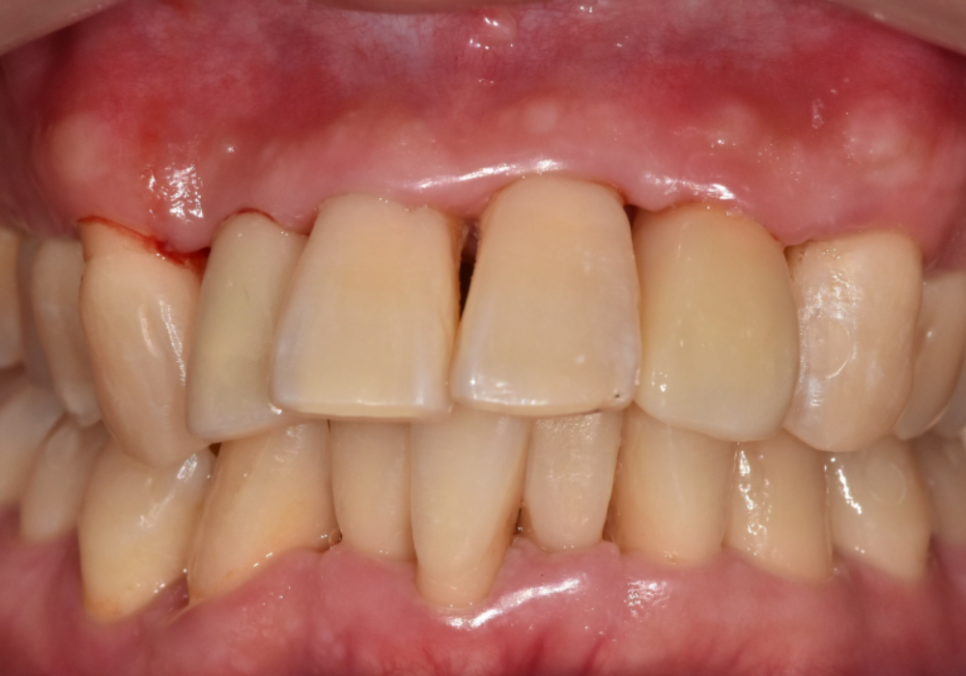

5개월 뒤, 짐작이 아닌

객관적인 데이터(기계 수치)로

완벽히 굳은 것을 확인한 후

최종 보철을 마쳤습니다.

251226

레진부터 임플란트까지

제각기 다른 치료가 들어갔지만,

사진을 보시면 주변 치아와

이질감 없이 아주 자연스럽죠?

치아의 색상과 투명도까지 하나하나

세밀하게 맞춘 덕분에,

어디 하나 튀지 않는

환한 미소가 완성되었답니다. ^^

250424(전) 251226(후)